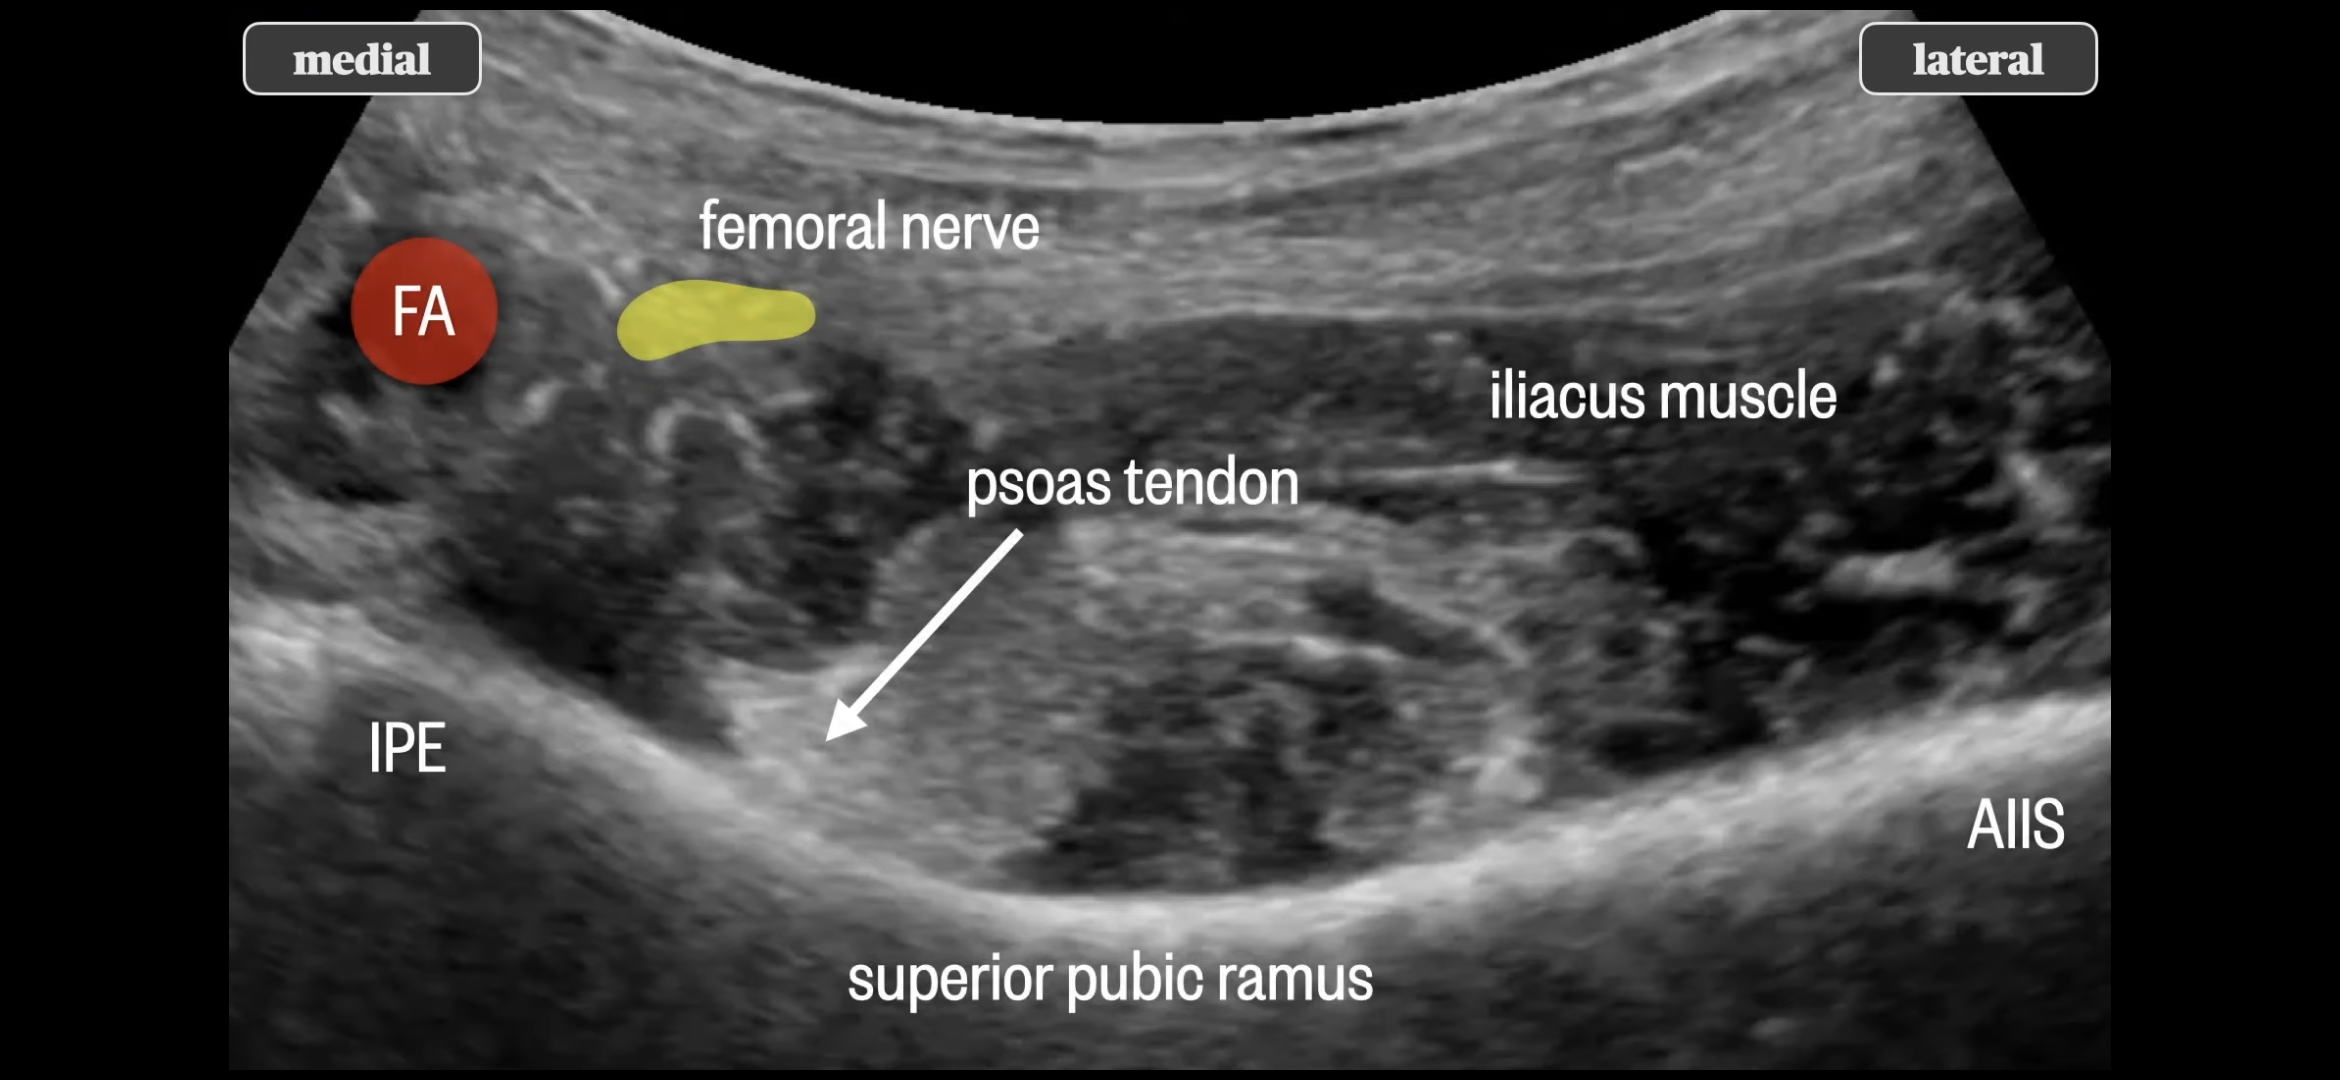

1. Pericapsular Nerve Group(PeNG) block

읽어 보니 사용한 방법은 두가지 신경 차단술이었다.

하나는 몇년 전부터 고관절 통증 관리, 특히 고관절 수술 후 통증 관리에 사용한 방법이고, 다른 하나는 내가 아는 신경 차단술이었다.

I. PeNG block

PeNG block + LFCN block